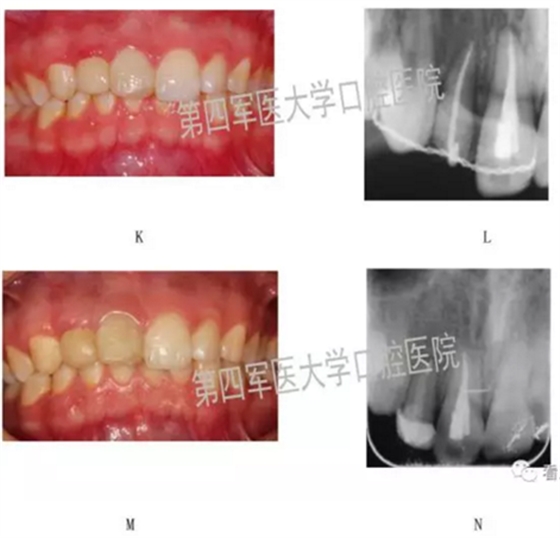

四、典型病例:

第四軍醫(yī)大學(xué)口腔醫(yī)院